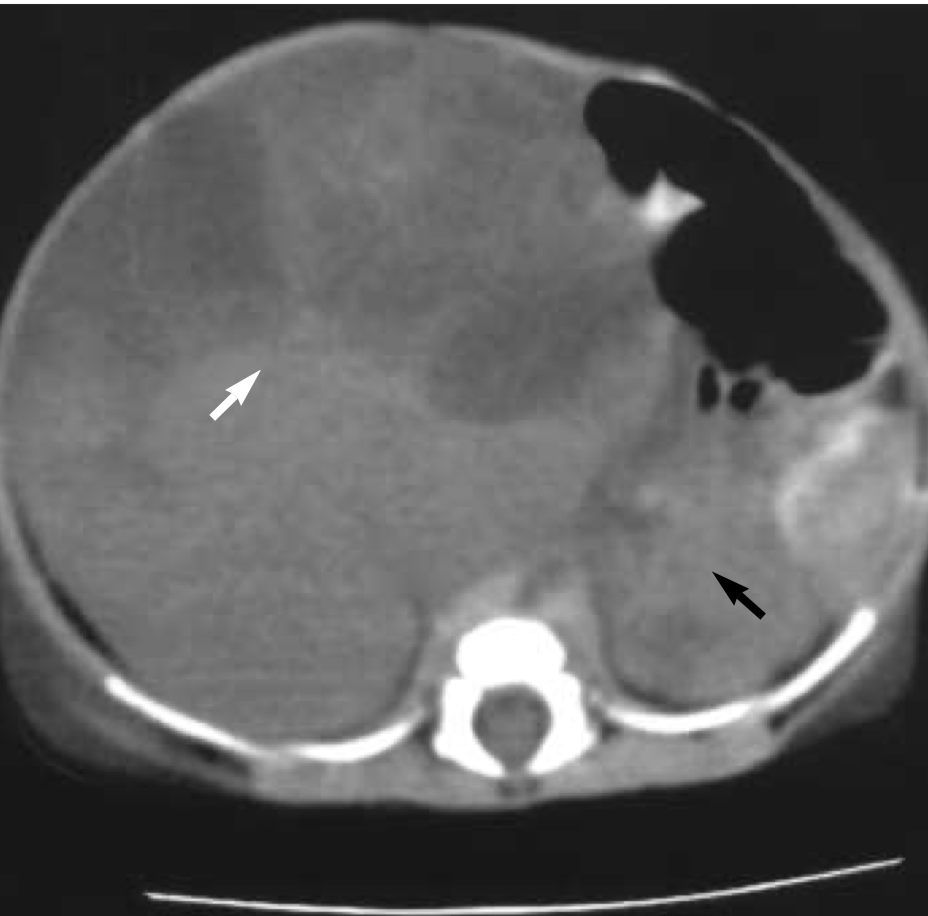

Upon admission to the NICU, the neonate exhibited a respiratiory rate 62/min, and blood pressure 69/43 mmHg. A physical examination revealed a prominent abdominal mass, measuring 7.5 cm in diameter on the right side of the abdomen, nearly occupying the abdominal cavity. The infant also presented with clubbed feet. Ultrasonographic examination and an abdominal CT scan unveiled a well-defined, heterogeneous, non-enhanced mass measuring 6.8 cm in diameter, originating from the right kidney, displaying both necrotic and cystic components. The left kidney appeared normal.

Sonographically, mesoblastic nephroma may present as a large (4 to 8 cm), unilateral renal mass with nodular densities, or as diffuse renal enlargement. These tumors are predominantly solid, but cystic areas are occasionally seen. Unlike Wilms’ tumor, there is no well-defined capsule, most likely due to hemorrhage with subsequent cystic degeneration.